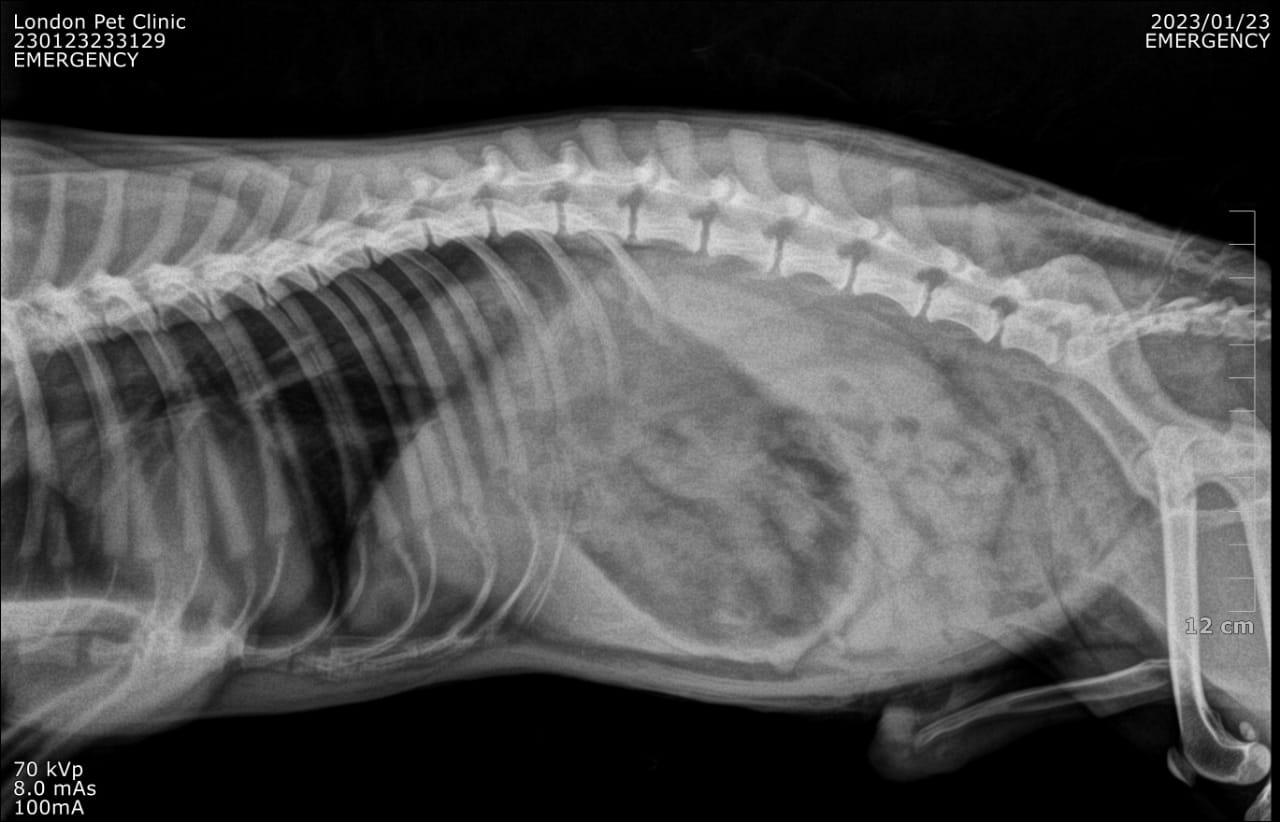

Post-operative X-Ray